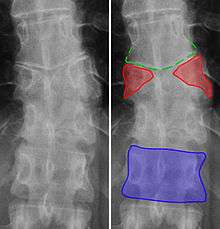

Transitional vertebrae

Transitional vertebrae have the characteristics of two types of vertebra. The condition usually involves the vertebral arch or transverse processes. It occurs at the cervicothoracic, thoracolumbar, or lumbosacral junction. For instance, the transverse process of the last cervical vertebra may resemble a rib. A transitional vertebra at the lumbosacral junction can cause arthritis, disk changes, or spinal cord compression. Back pain associated with lumbosacral transitional vertebrae (LSTV) is known as Bertolotti's syndrome. One study found that male German Shepherd Dogs with a lumbosacral transitional vertebra are at greater risk for cauda equina syndrome, which can cause rear limb weakness and incontinence.[6]